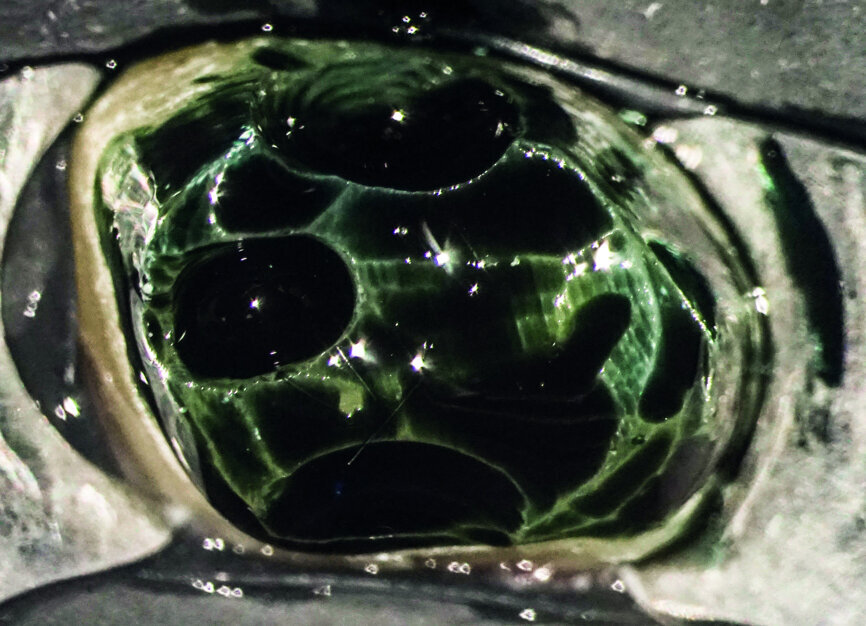

After isolation of the tooth (Fig. 3), an access cavity was created using high-speed diamond burs and ultrasonic tips (Figs. 4–8). Pre-flaring in the coronal and middle thirds was done with the HyFlex EDM 25 instrument (at a torque of 4 Ncm and a speed of 500 rpm). It is a proven fact that pre-flaring allows an increase in the instrument size that binds in the root canal, irrespective of the discrepancy between the size of the file and anatomical diameter. [19–21] Afterwards, canal scouting was performed using an ISO size 10 stainless-steel K-file up to working length. Upon establishing the working length, with the help of an apex locator, the 10/05 EDM file (glide path file) was used up to working length (at a torque of 3 Ncm and a speed of 300 rpm). Subsequently before finishing the preparation with the 25 EDM file, the 20/05 EDM (preparation file) was used to full working length (at a torque of 3 Ncm and a speed of 400 rpm). At this point, the working length was confirmed again with an ISO size 20 NiTi K-file. Root canal shaping was completed with the 25 EDM file, which was inserted to full working length (at a torque of 3 Ncm and a speed of 400 rpm; Figs. 9–12).

After chemomechanical treatment, the root canals were filled using a single-cone filling technique (ROEKO Guttapercha Points and ROEKO GuttaFlow bioseal, both COLTENE), and the access cavity was sealed using composite materials (Figs. 12–16).